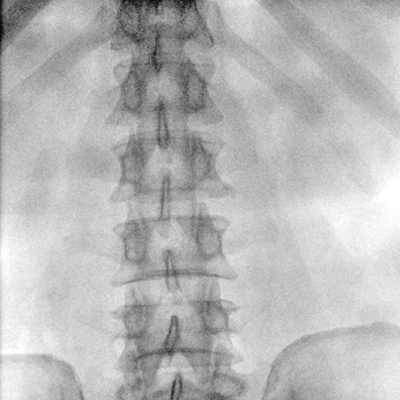

臨床適用科室:骨科、普通外科、矯形外科、創(chuàng)傷外科、泌尿外科、脊柱外科、疼痛外科、消化科、婦科等科室。

大尺寸動態(tài)平板探測器,高DQE、低噪聲、圖像清晰。采用多分辨率圖像增強處理技術(shù),不同部位不同圖像處理算法,滿足客戶多樣化的需求。

采用智能變頻脈沖透視技術(shù),優(yōu)化圖像質(zhì)量的同時降低輻射劑量,呵護醫(yī)患健康